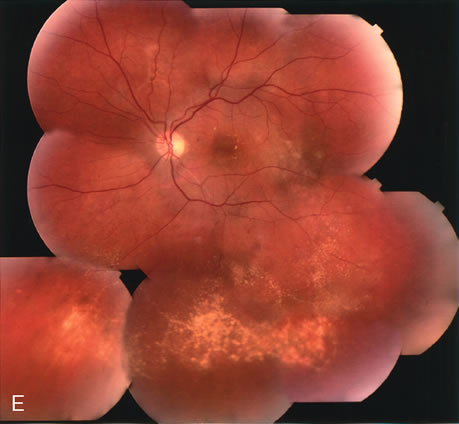

Fig. 20. A. Red-free photograph of a 20-year-old patient with sudden loss of vision to the level of 20/200. There is exudative, neurosensory macular detachment, a few hemorrhages, and lipid exudates. B. Fluorescein angiography reveals the presence of classic choroidal neovascularization (CNV), which appears to be juxtafoveal (<200 μ from fixation). Given the size of the CNV and its proximity to the fovea, it was decided to treat the patient with photodynamic treatment (PDT). C. Red-free photograph of the same eye 2 weeks after PDT; there is increased subretinal exudation D. Fluorescein angiography demonstrates that the CNV is still actively leaking. E. Red-free photograph 4 weeks after PDT demonstrates further increase in the size of the neurosensory macular detachment, subretinal hemorrhages, and lipid exudation. F. Fluorescin angiography reveals that the CNV has extended under the fovea. Given the young age of the patient, an inflammatory component of the neovascular process was suspected. It was decided to give a posterior, subtenon injection of triamcinolone acetonide, 40 mg/1 mL. G. Two weeks after steroid treatment there is partial reabsorption of the subretinal fluid. H. Fluorescein angiography demonstrates contraction of the CNV. I. Four weeks after injection of triamcinolone there is further reduction in the degree of neurosensory detachment; vision had improved to 20/60. J. Fluorescein angiography demonstrates that the CNV is smaller and less active (less leakage).